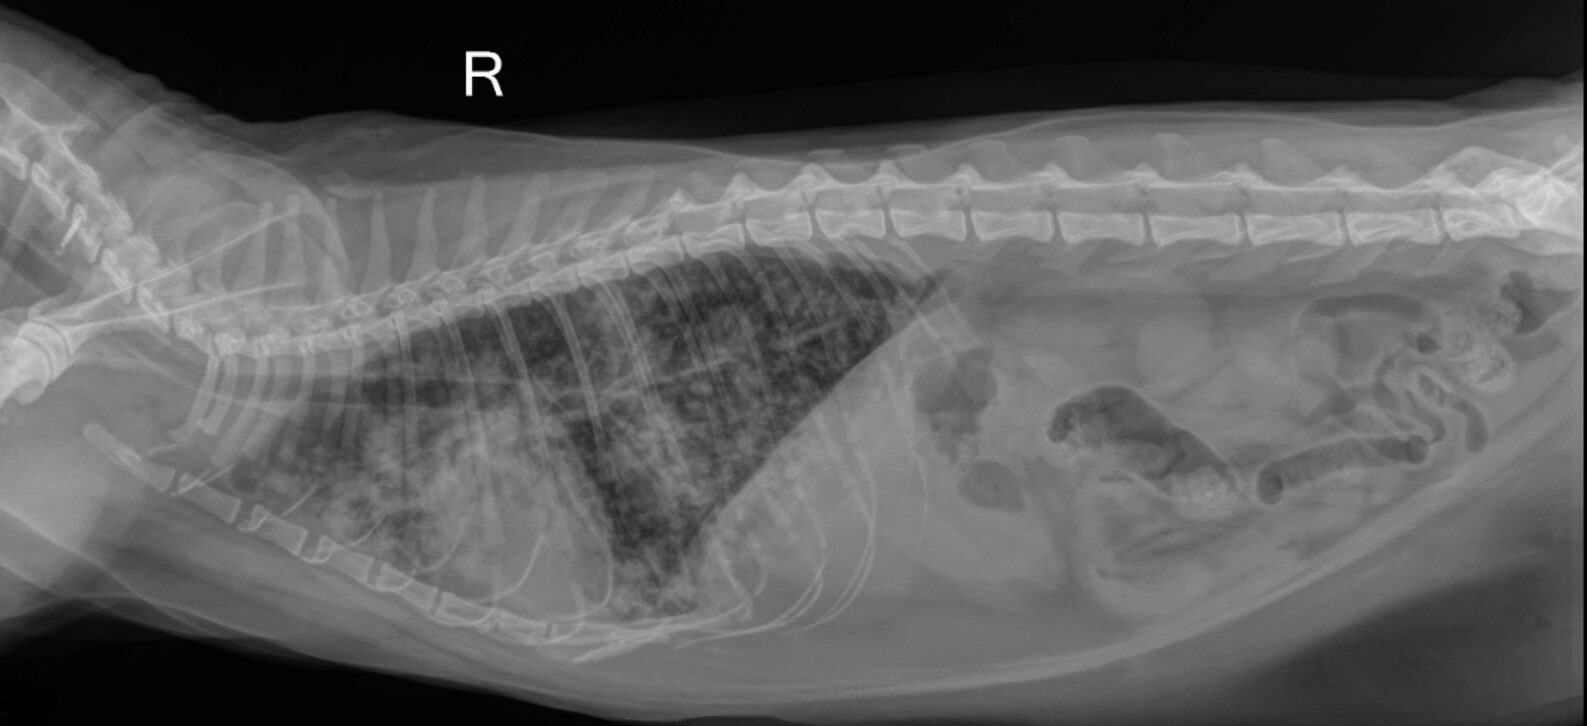

Die initiale Blutuntersuchung ergab eine Leukopenie und erhöhte Leberwerte. Diese Befunde ließen eine systemischen Infektion vermuten, wobei insbesondere eine Toxoplasmose in Betracht gezogen wurde. Ein serologischer Test auf Toxoplasma gondii wurde am selben Tag eingeleitet, um die Verdachtsdiagnose zu bestätigen. Zusätzlich wurde ein Röntgenbild des Thorax angefertigt, das eine beidseitige pulmonale Infiltration und perihiläre Verdichtungen aufzeigte. Die serologischen Resultate waren positiv und bestätigten das Vorhandensein von Antikörpern gegen Toxoplasma gondii. Im Gesamtkontext wurde daher der Verdacht auf eine Toxoplasmose erhärtet, die aufgrund der Immunsuppression der Katze und Kontakt zu potentiellen Überträgertieren begünstigt wurde.